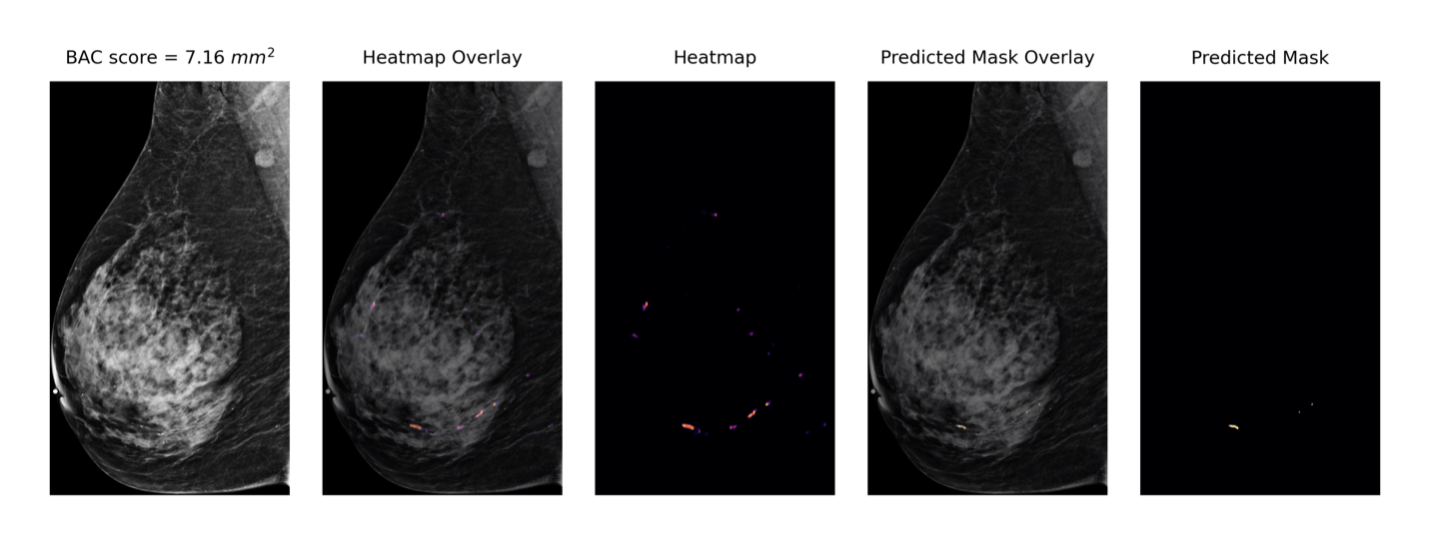

Figure 1: Examples of mammograms with mild, moderate and severe BAC quantified by our AI model.

BAC severity was categorized into four groups based on the quantified BAC area: No BAC (0-2 mm2), Mild (2-10 mm2), Moderate (11-40 mm2) and Severe (¿40 mm2) (Figure 1). These thresholds were established through empirical analysis that maximized between-group hazard ratio differences in an independent Emory patient cohort (Supplemental Figure A2). The No BAC category’s upper threshold of 2 mm2 was chosen to account for potential image noise artifacts, which was validated through visual inspection of 100 exams.